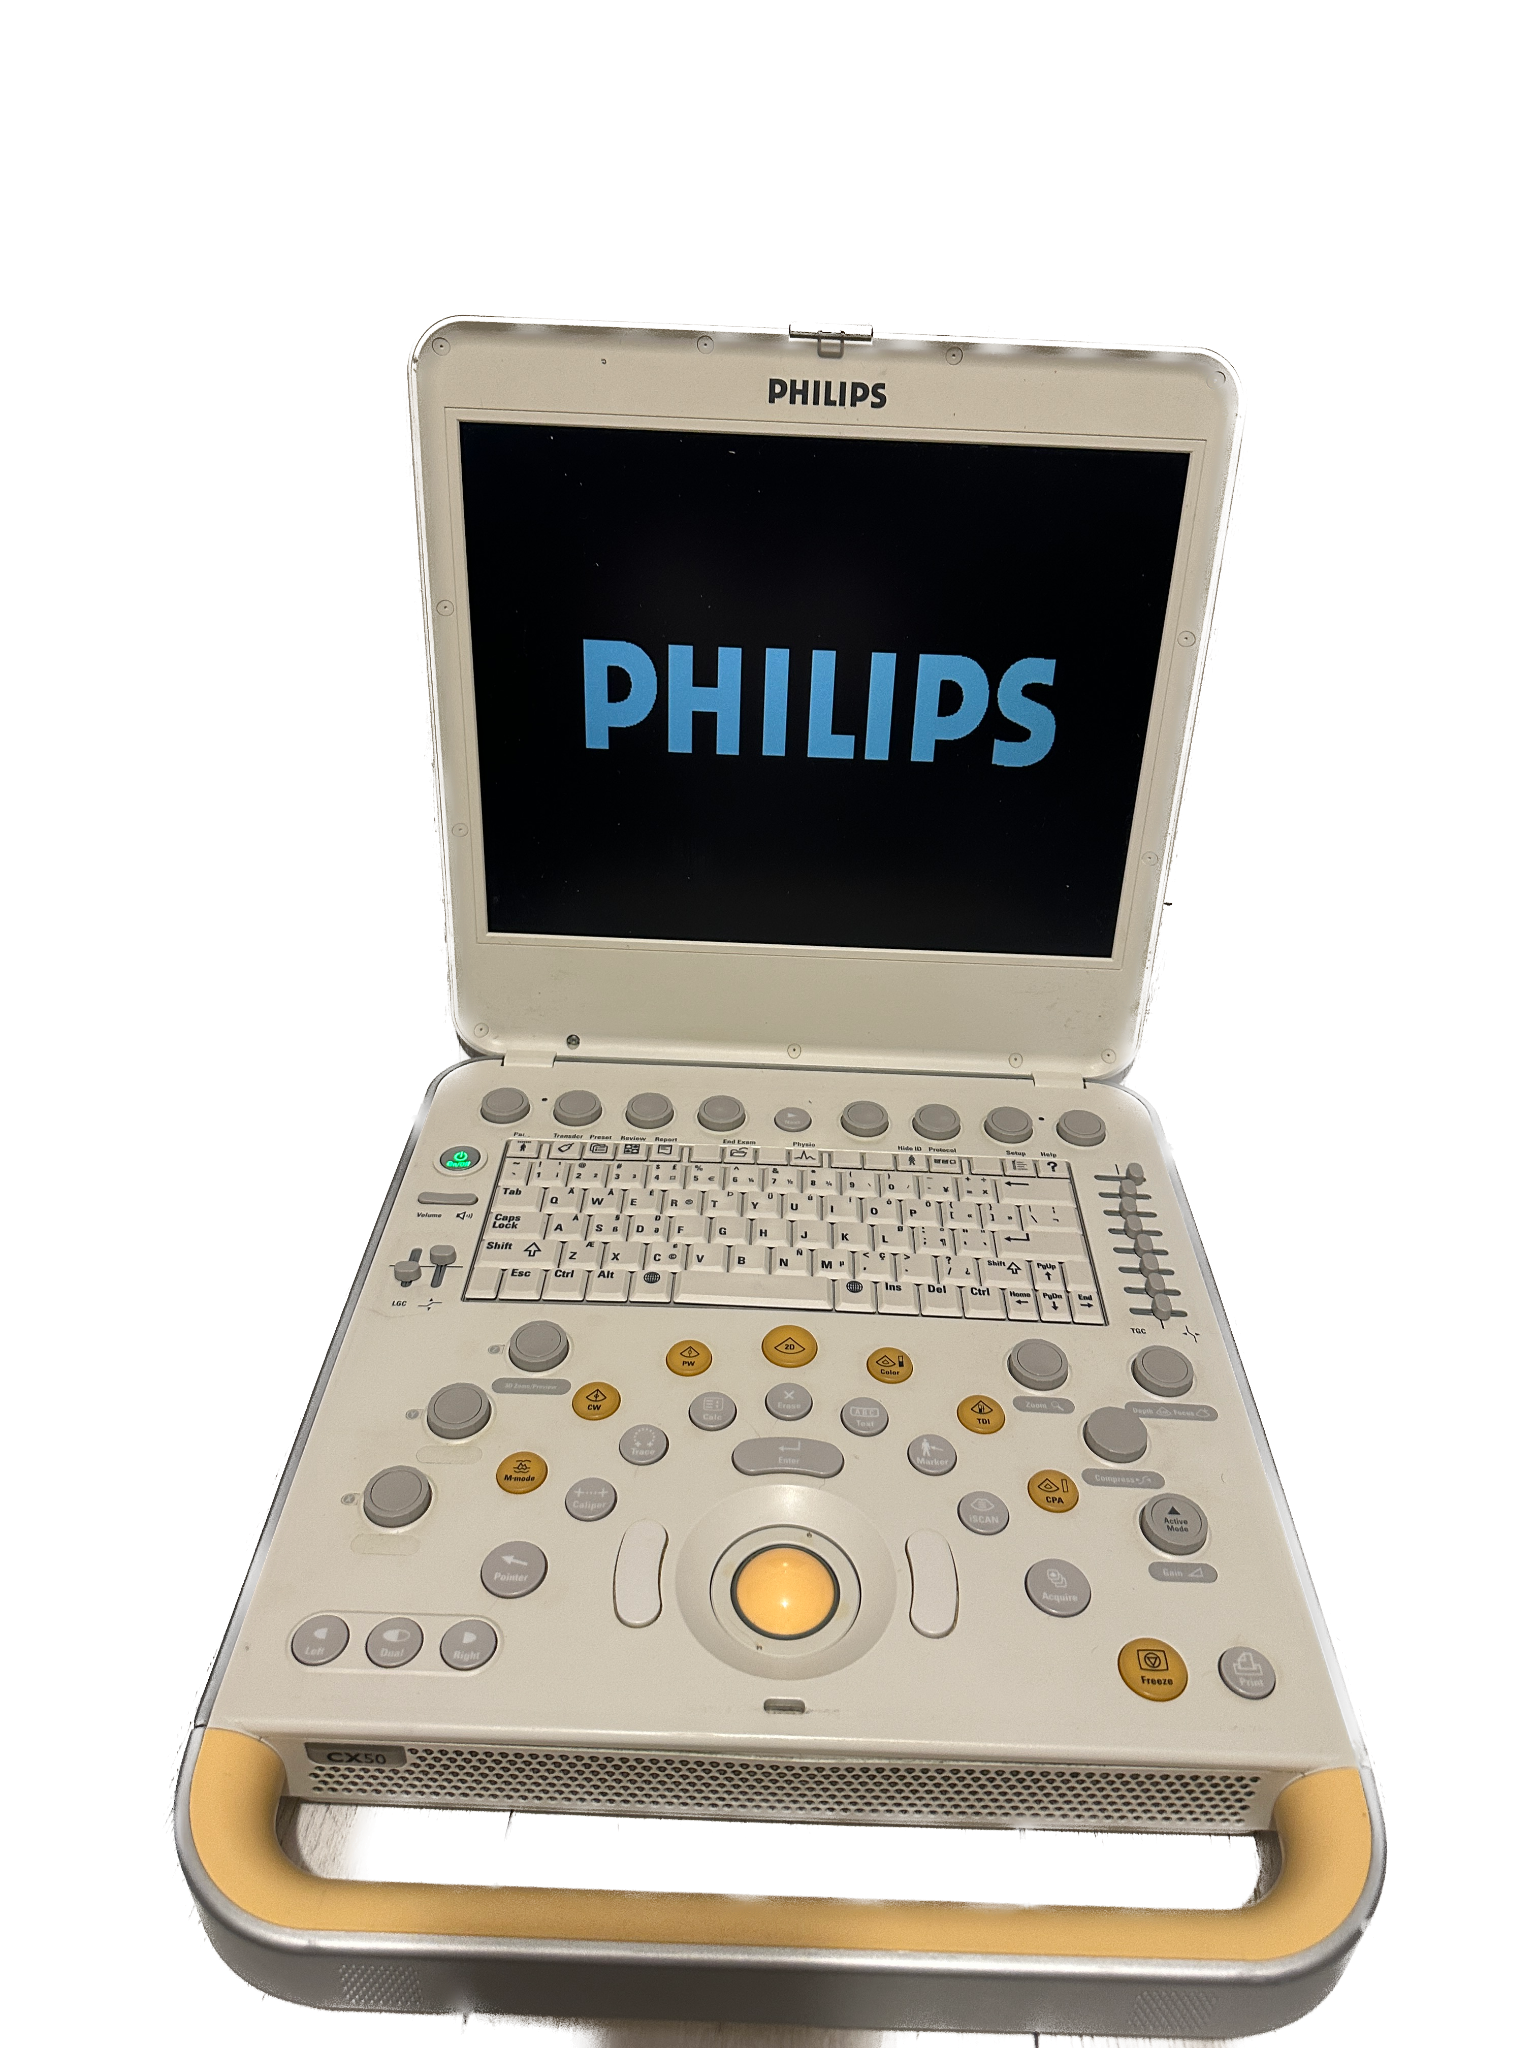

DIAGNOSTIC ULTRASOUND MACHINES FOR SALE

GE RSP6-16-RS Ultrasound Volumetric Probe 2011

Sale price$ 6,690.08